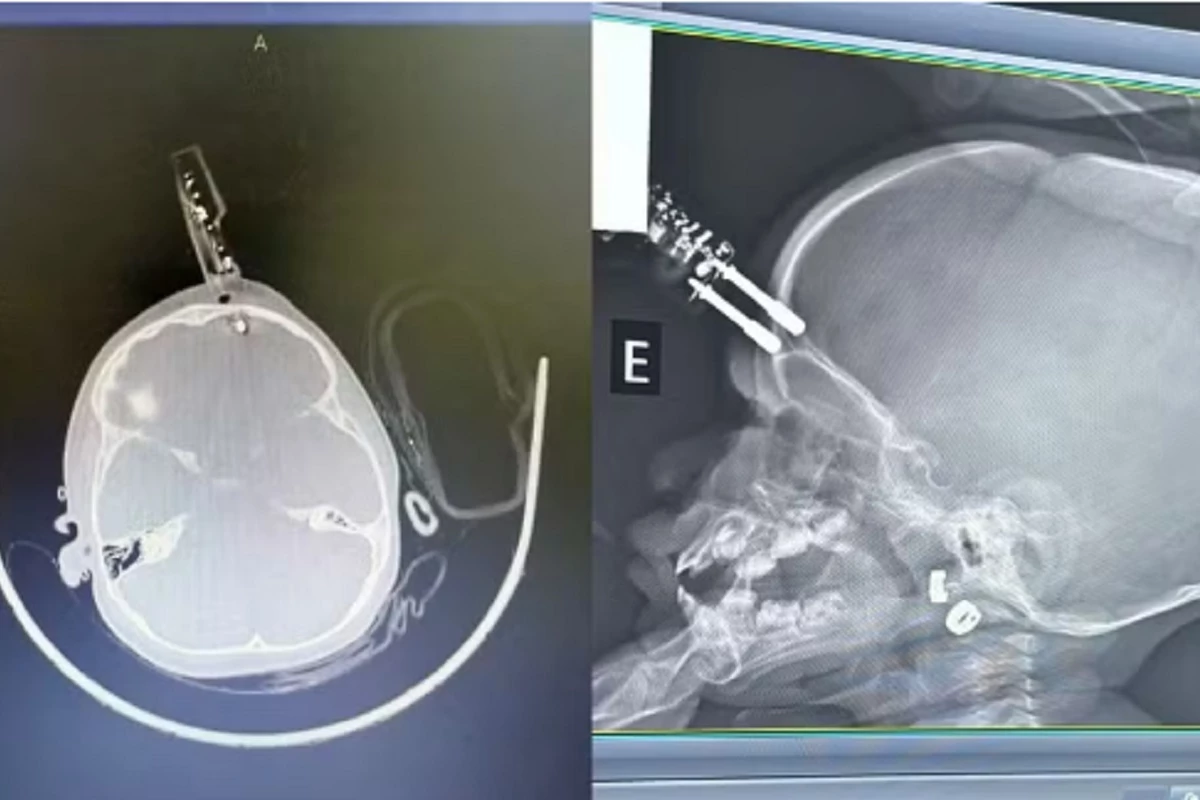

Uma menina de um ano foi submetida a uma cirurgia de urgência em Divinópolis, na região Centro-Oeste de Minas Gerais, após cair da cama e ficar com um carregador de celular cravado na testa. O acidente doméstico ocorreu na última terça-feira (13) e a criança permanece internada em observação, sem apresentar sinais de sequelas neurológicas até o momento. O objeto perfurou a região frontal do crânio, atingindo uma área muito próxima ao olho, o que exigiu intervenção imediata da equipe de neurocirurgia para a retirada segura do material e o tratamento da lesão traumática.

O neurocirurgião Bruno Castro, responsável pelo atendimento, relatou ter recebido a informação de que a mãe da criança havia se afastado momentaneamente para ir ao banheiro quando a queda aconteceu. A principal hipótese médica é que a menina segurava o carregador ao cair, o que causou a perfuração do osso e o contato direto com o tecido cerebral. O médico explicou que o trauma representava riscos severos, incluindo a possibilidade de hemorragia interna e infecção grave, uma vez que o objeto rompeu as barreiras naturais de proteção do corpo. Apesar da gravidade da situação, a visão da paciente foi preservada.

A criança foi encaminhada ao bloco cirúrgico para procedimentos de limpeza, retirada do corpo estranho e reconstrução da área atingida. A agilidade no procedimento médico foi considerada fundamental para minimizar os danos causados pelo empalamento e prevenir complicações imediatas.